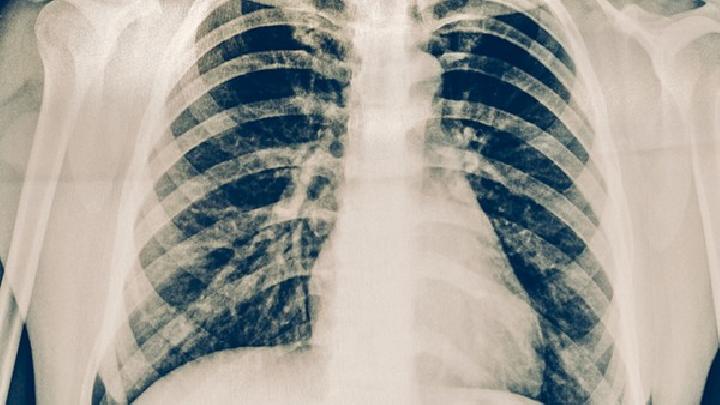

吕弗琉于1932年首次描述了这种疾病,因此又称吕弗琉综合征。其特点是游走性肺浸润伴外周血嗜酸粒细胞计数增加,肺部症状轻微,多为轻咳,病程自限,常见3~4周内自愈。

单纯性肺嗜酸粒细胞浸润症是什么?